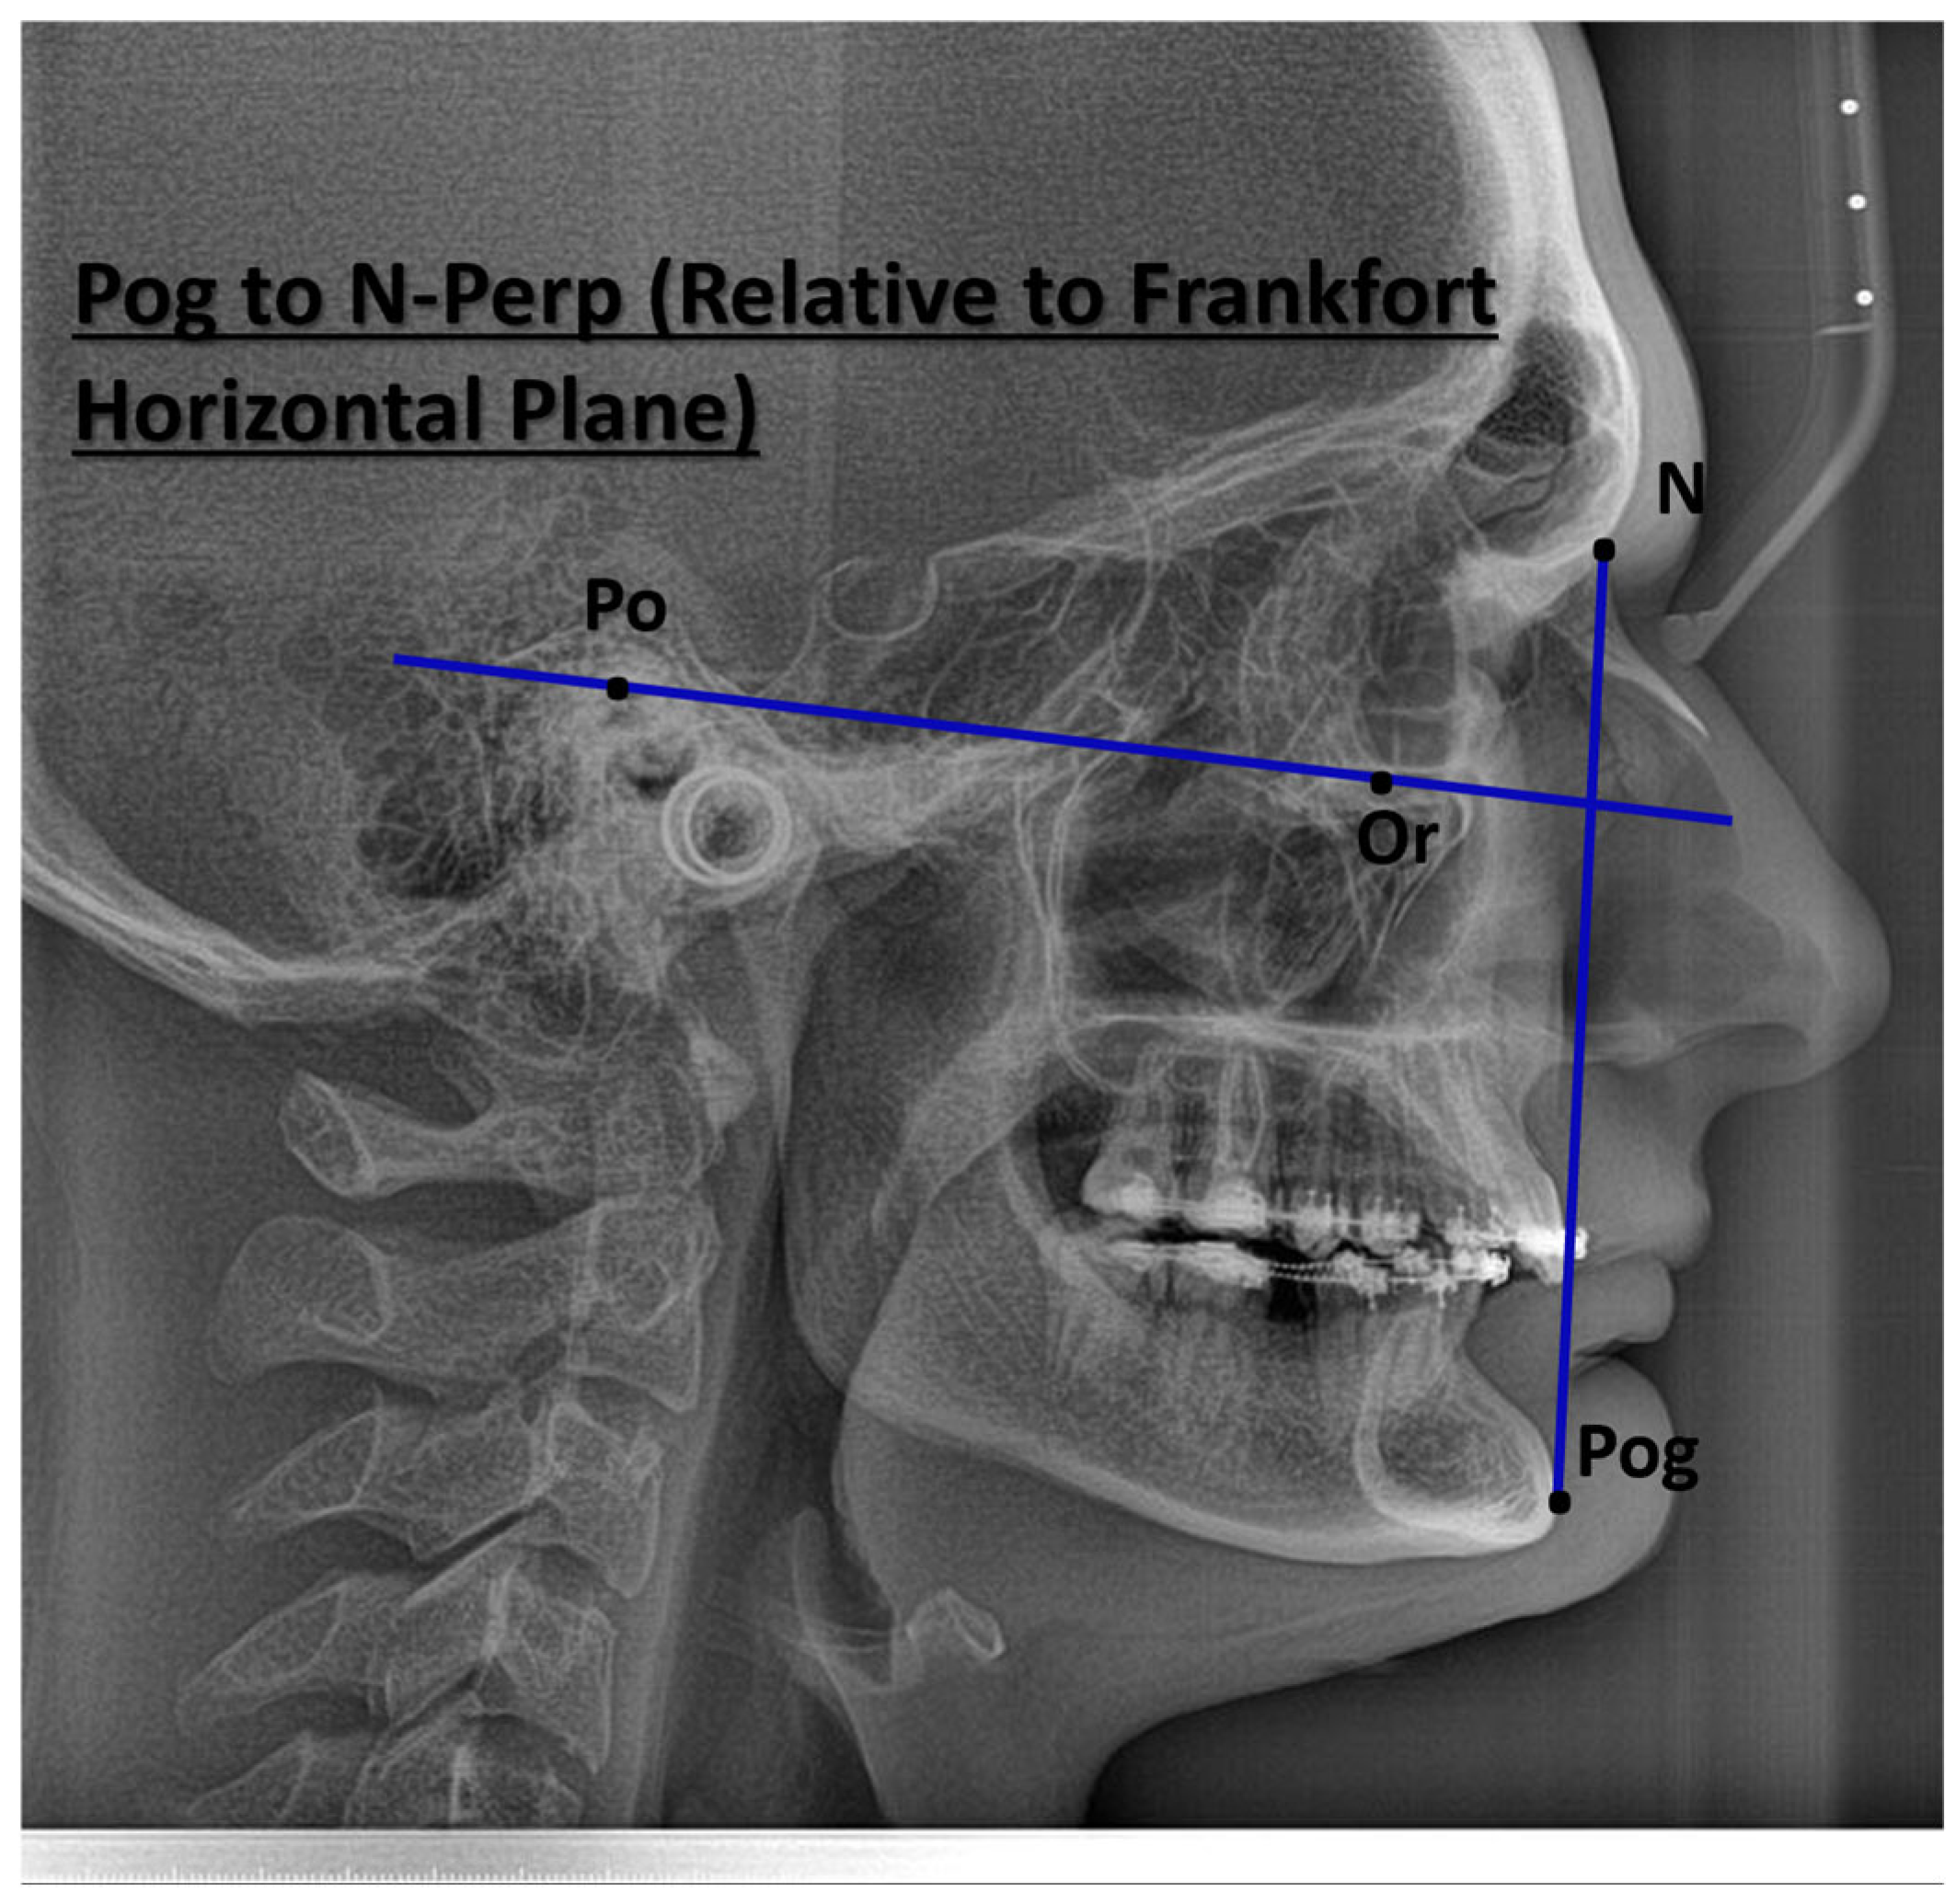

| Pogonion to N-Perpendicular FH (mm) | 1.87 (−0.94, 2.31) | 1.4 (0.4, 2.6) |

| Pogonion to N-Perpendicular FH (mm) | −1.571 | 1.21 | −1.296 | 24 | 0.207 |